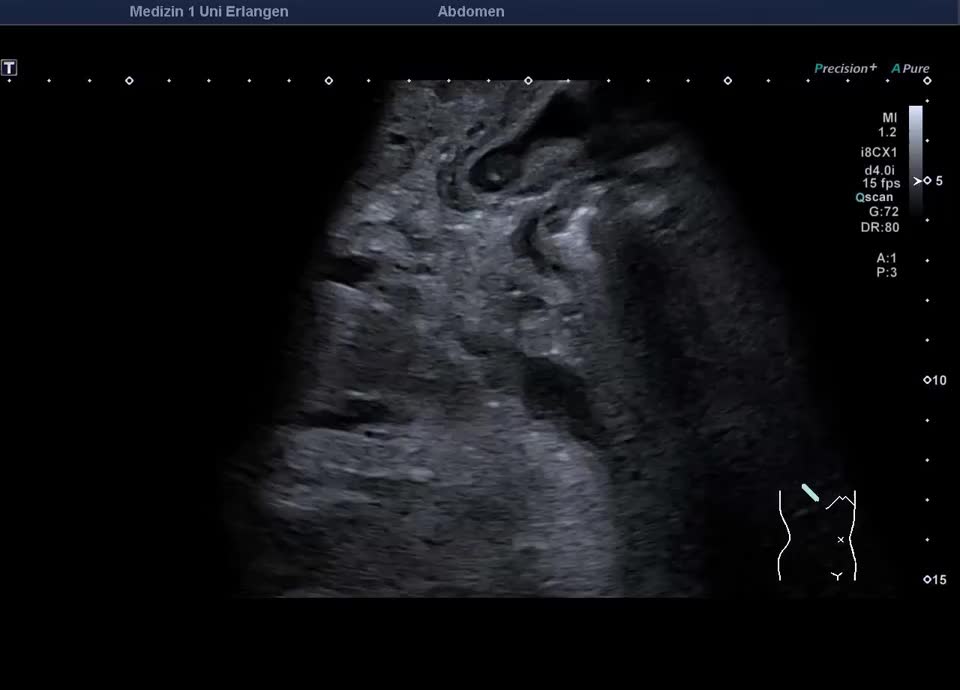

71-jähriger Patient mit Z.n. Duodenalkarzinom und Tumorresektion mit Duodeno-Jejunostomie. Circa ein Jahr nach Resektion zeigt sich im Ultraschall eine intra- und extrahepatische Cholestase mit Cholangitis. In der ERCP zeigt sich ein Tumorrezidiv mit exophytisch wachsender Tumorstruktur in der Papillenregion, die Sondierung der Papille gelingt nicht. Am Folgetag wird eine Choledochoduodenostomie mit Einbringung eines Lumen-Apposing Metal Stent (LAMS) endosonographisch durchgeführt. Hierbei entleert sich reichlich trübe Galle. Die Folgeuntersuchung nach drei Tagen zeigt eine Aerobilie (-> somit Beweis der korrekten Lage des Stents).